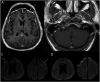

Results: Seventy-four patients were identified (42/57% male, median age 64 years). The majority of patients self-identified as Black or African American (38, 51%). The most common neurologic symptoms at presentation to the hospital included altered mental status (39, 53%), fatigue (18, 24%), and headache (18, 18%). Fifteen patients had ischemic strokes (20%). There were 10 in-hospital mortalities, with moderately severe disability among survivors at discharge (14%, median modified Rankin Scale score of 4).

Conclusions: Neurologic findings spanned inflammatory, vascular pathologies, sequelae of critical illness and metabolic derangements, possible direct involvement of the nervous system by SARS-CoV-2, and exacerbation of underlying neurologic conditions, highlighting a broad range of possible etiologies of neurologic complications in patients with coronavirus disease 2019 (COVID-19). Further studies are needed to characterize the infectious and postinfectious neurologic complications of COVID-19 in diverse patient populations.